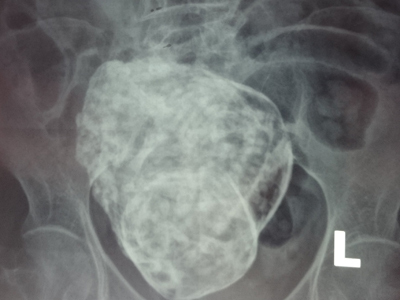

Cô Mercy James và con gái |